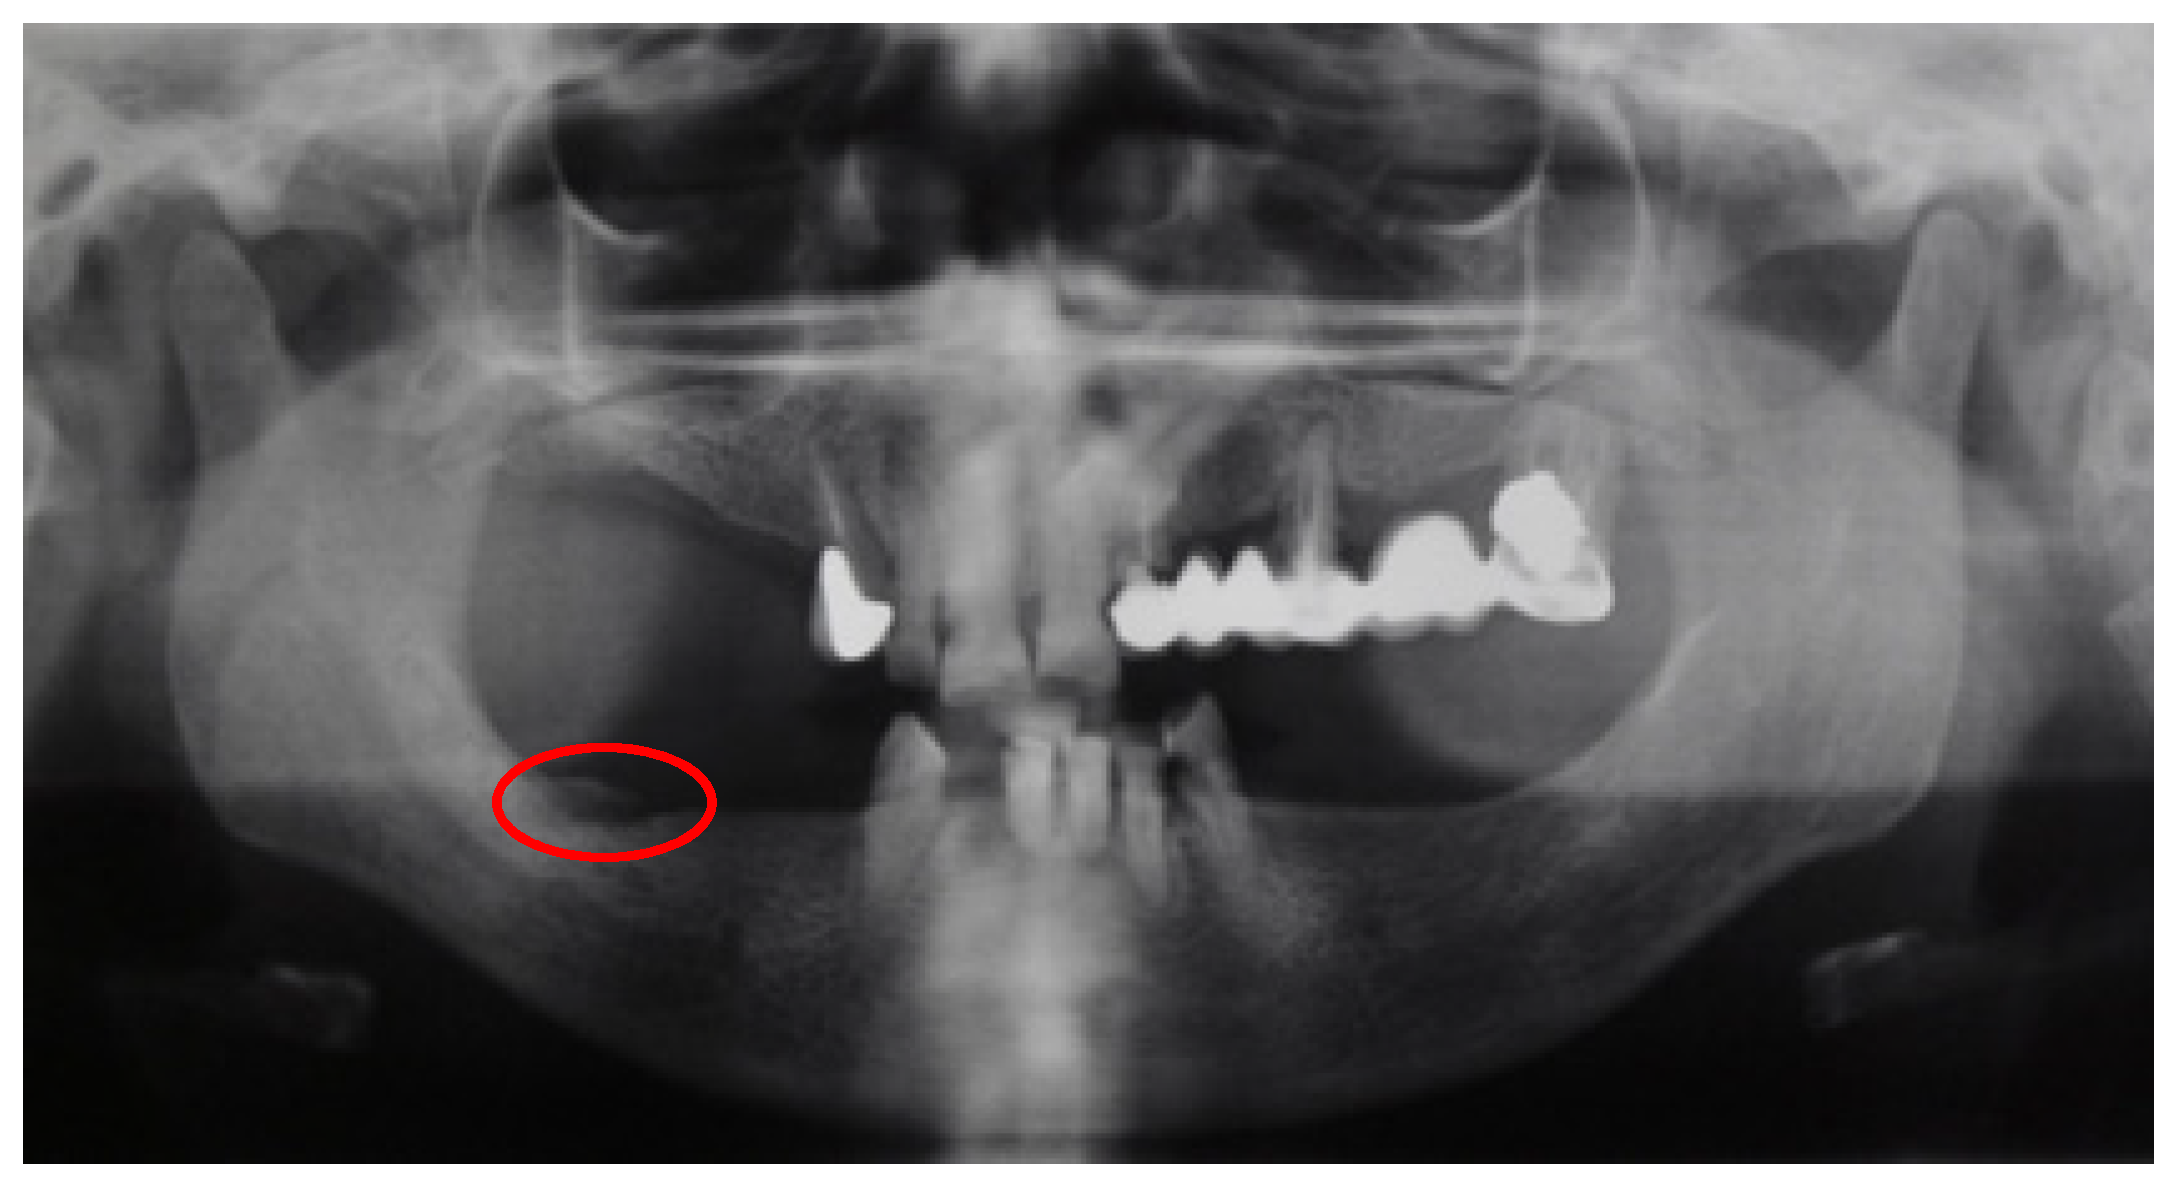

| Patient | Age | MRONJ Stage |

|---|---|---|

| Patient 1 | 44 | I |

| Patient 2 | 79 | II |

| Patient 3 | 61 | II |

| Patient 4 | 69 | I |

| Patient 5 | 85 | III |

| Patient 6 | 77 | I |

| Patient 7 | 65 | I |